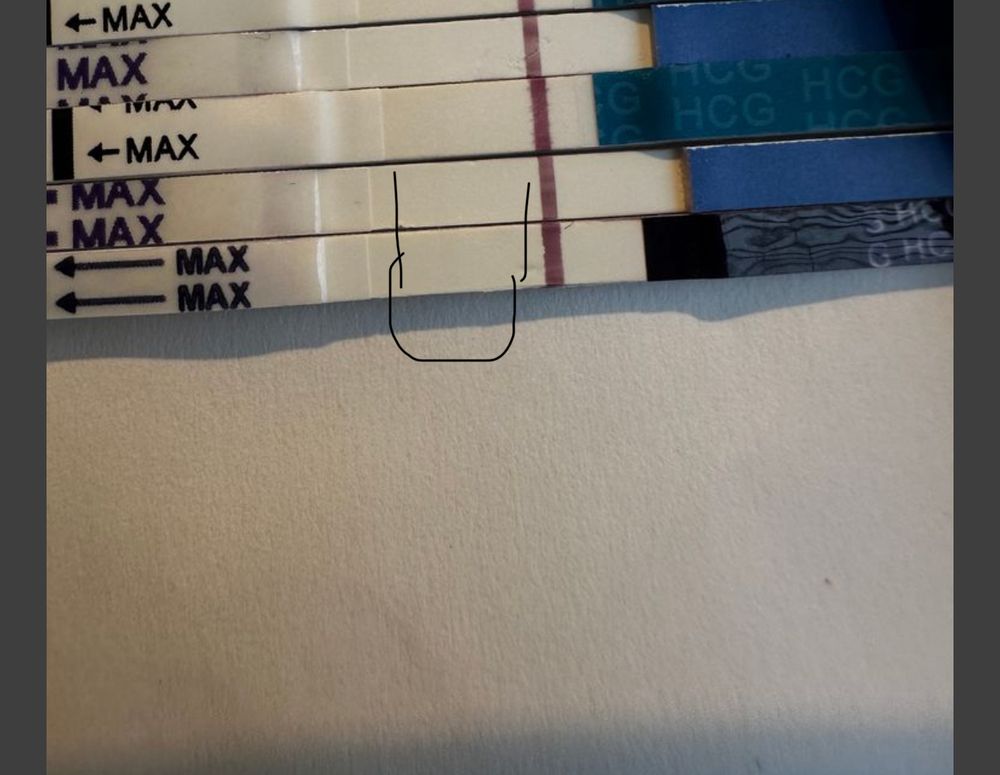

Что вы видите и видите ли вообще 😁

я вижу здесь розовенькие полосочки но честно им не верю что вы скажете? Последний тест прогнала через прогу полоска вроде мне не мерещиться не знаю даже

А как смотреть снизу вверх или наоборот? На верхнем есть //

Таня Орозова, верхние там есть полоски это хгч укол снизу вверх мне вот интересно на нижнем видно или нет его еще так сложно сфоткать 🥲🤦🏻♀️